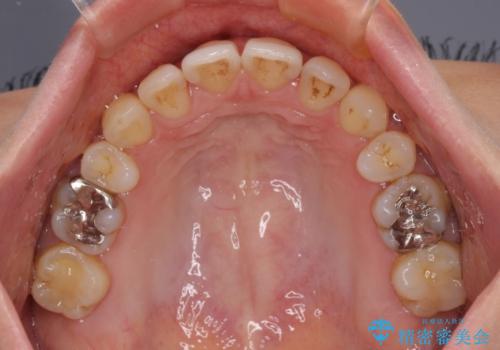

上顎前歯の突出を軽減 インビザラインによる抜歯矯正

- 上の前歯の突出感を気にして来院された患者様です。

目立たない装置を希望とのことで、上顎左右第一小臼歯を抜歯し、インビザラインにて矯正治療を行うこととしました。